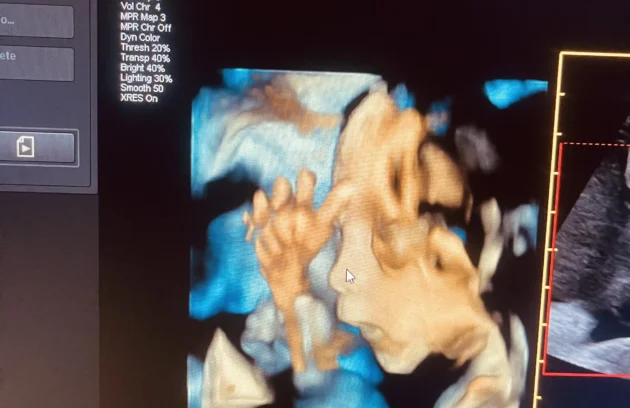

🔹 3D / 4D Ultrasound

3D/4D Ultrasound provides a clear and real-time view of your baby inside the womb. While 3D shows detailed images, 4D allows you to see live movements like smiling or yawning. It enhances bonding between parents and baby while also helping doctors assess physical development. Experience advanced 4D ultrasound in Kathmandu for a memorable and informative pregnancy journey.